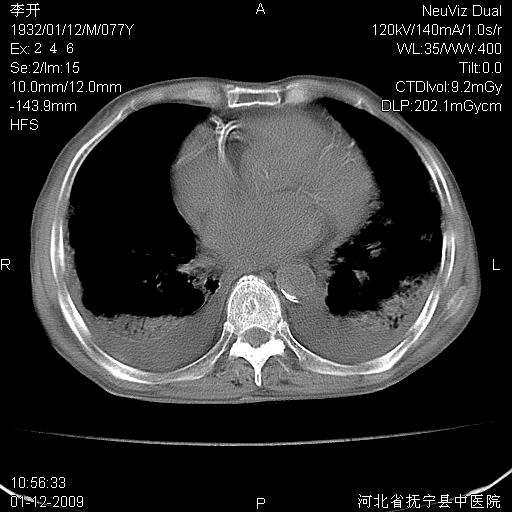

以下是引用黑白光影在2009-1-19 16:49:00的发言:[br]心衰肺水肿;心包、胸腔积液;冠脉钙化;肺部感染。